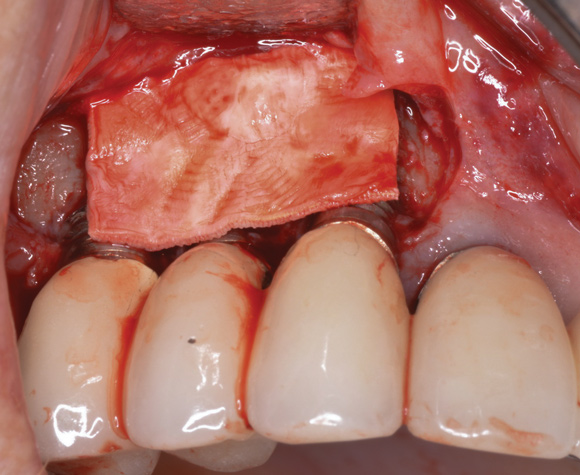

(17.) A cross-linked collagen bone graft scaffold is applied over the debrided implant surfaces to help reconstruct a portion of the deficient buccal bone.

Figure 17

(18.) A subepithelial, connective tissue graft from the palate is affixed over the collagen bone scaffold and around the abutments of the three involved implants.

Figure 18